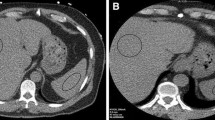

VNC and iodine maps were generated using vendor-supplied software (Siemens Syngovia) using the “Liver VNC” setting. Regions of interest (ROI) were placed in the right and left hepatic lobes of the “mixed” (120 kVp-equivalent) images. Each ROI had an area measuring approximately 5–6 cm2. ROIs were placed in central regions of the right and left hepatic lobes, and care was taken to avoid placing ROIs on hepatic vasculature. For each ROI, the HU of the VNC image as well as the mixed 120 kVp-equivalent image were recorded. ROIs were subsequently placed in matching locations within the right and left hepatic lobes within MRI-derived fat fraction maps. Examples of ROI placement in situations of normal and elevated liver fat are illustrated in Fig. 2.

Representative patient images used for analysis. a Concordant-negative example: single axial slice from the combined 120 kVp-equivalent 30-year-old inpatient using dual-source DECT. b VNC DECT image with a circular ROI placed in the right hepatic lobe (82 HU). c MRI PDFF image with an ROI in the same location shows no fatty liver (PDFF = 0.5%). d Concordant-positive example: 120 kVp-equivalent axial image from a 29-year-old scanned in the emergency department using a split-beam DECT. e DECT VNC image with ROI placed in the right hepatic lobe showing decreased attenuation (24.3 HU). f MRI PDFF image at the same location showing markedly elevated liver fat (PDFF = 24.3%). This figure also contains the ROI used for the left lobe in this subject (arrow). The anatomically matched corresponding CT ROI was located on a different slice. g Discordant example: 120 kVp-equivalent axial image from a 30-year-old scanned in the emergency department using a split-beam DECT. h DECT VNC image with ROI placed in the right hepatic lobe showing normal attenuation (70.4HU). i MRI PDFF image at the same location showing elevated liver fat (PDFF = 13.8%). The outer yellow contours in panels f and i (arrowheads) correspond to the vendor’s automated liver segmentation (burned into the image) and was not part of our analysis. DECT dual-energy CT, VNC virtual non-contrast, PDFF proton density fat fraction